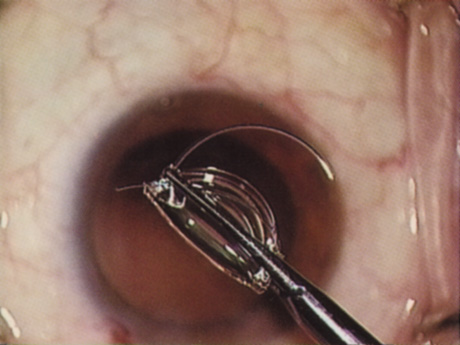

Capsulorrhexis can be performed with a cystitome, capsulorrhexis forceps, or combination-type instruments. Regardless of which instrument is used, several principles can help the surgeon successfully complete capsulorrhexis. It is important to maintain the anterior chamber, because making the chamber shallow increases tension on the zonules and causes the tear to run peripherally. The authors recommend the use of a viscoelastic agent for maintaining chamber depth and, of course, for endothelial protection. Therefore, if the tear begins to run peripherally, the surgeon should redeepen the anterior chamber before attempting to redirect the tear. Additionally, folding the capsule margin can aid the surgeon in redirecting the tear more accurately (Fig. 10).

Fig. 10. The capsulorrhexis tear is more easily redirected by folding the capsule over, in advance of the tear.